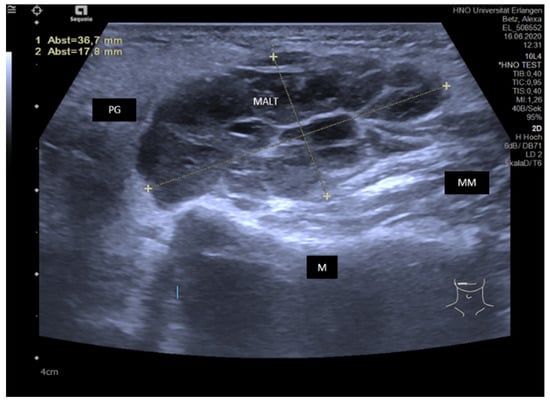

3.4.3. Sjoegren’s Syndrome/Disease